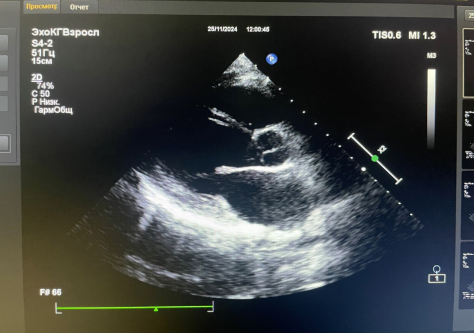

Рис. 4. Фото трансторакальной ЭхоКГ от 25.11.2024. Парастернальная позиция по длинной оси ЛЖ.

Амбулаторное обращение. Жалоб нет. АД 105/60 мм рт.ст. ЧСС 80 уд./мин. ЭхоКГ: разрастание эндокарда верхушки и передне-боковой стенки ЛЖ с распространением на заднюю створку МК. Рестрикция задней стенки МК. НМК 3 ст., НТК 2 ст. Расширение ЛП. ФВ ЛЖ 53%. СДЛА 38 мм рт.ст. (рис. 3, 4). Поддерживающая терапия: метилпреднизолон 4 мг 3 таблетки в сут. |